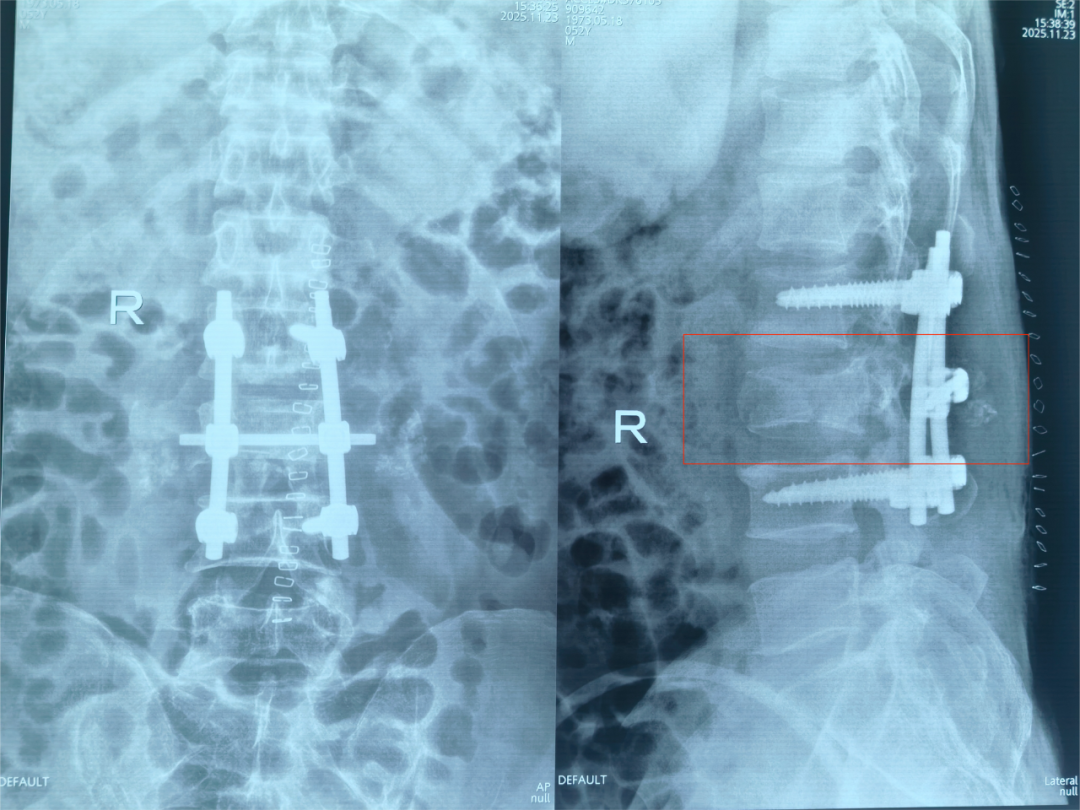

该院骨科团队联合麻醉科、手术室、影像科等多学科专家,迅速为患者制定了详尽的手术方案:后路腰3椎体爆裂骨折切开复位、椎管减压术。手术的核心目标非常明确:第一,彻底解除对脊髓的压迫,为神经功能恢复创造空间;第二,重建脊柱的稳定性,为患者日后站立和行走打下基础。

手术由刘邦定主任主刀,杨鑫、谢犇、张强医师等密切配合。术中,团队以精湛的技艺小心翼翼地避开重要的神经和血管,精准置入内固定物,然后如同“微雕”一般,将压迫在脊髓上的碎骨块一点一点地取出,彻底解除了脊髓的“枷锁”,实现了完美的椎管减压。整个手术过程如履薄冰,但团队操作行云流水,成功完成了预定目标,患者即表示下肢出现了麻木感,这是一个积极的信号!病人麻醉清醒后患者双下肢立即恢复了运动,双侧膝踝关节可以屈伸活动,双侧足趾也出现了勾脚活动。